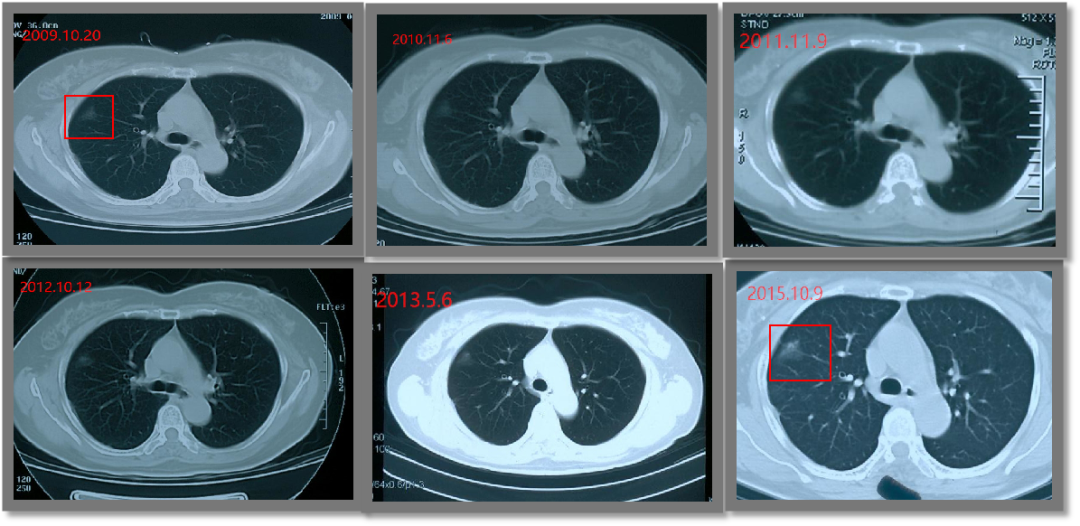

持久战!磨玻璃结节竟随访14年 2006年,张女士在一次偶然的体检中发现自己右肺上有个磨玻璃结节(GGO)。 由于之前因肾癌开过一...